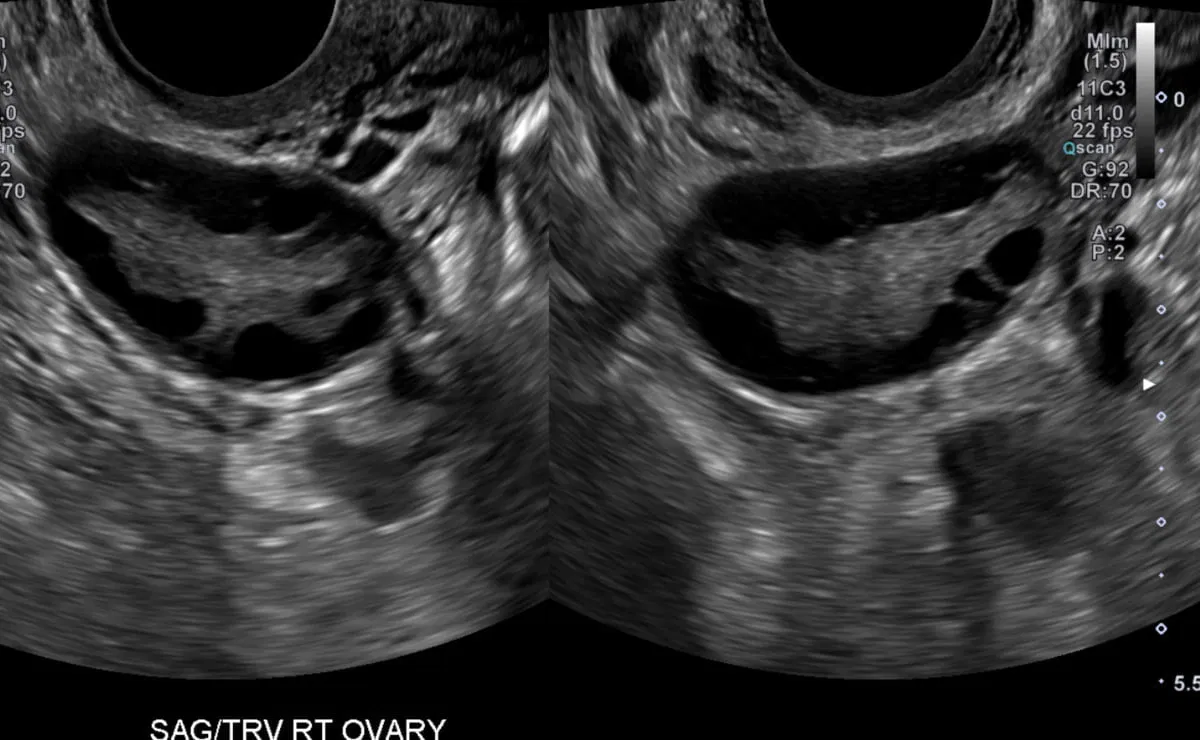

- Ovarian volume calculator (useful for ultrasound diagnosis of polycystic ovaries). In patients with PCOD/PCOS (Polycystic ovarian syndrome/disease) the ovarian volumes are usually more than 10cc. Check the examples below

- Calculate the volume of ovarian cysts.